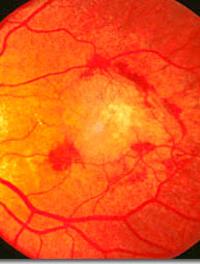

La dégénérescence maculaire liée à l’âge (DMLA) est la principale cause de malvoyance chez les plus de 50 ans en Europe et en Amérique [...]

La dégénérescence maculaire liée à l’âge est extrêmement fréquente, elle est systématiquement l’une des trois premières causes de cécité [...]